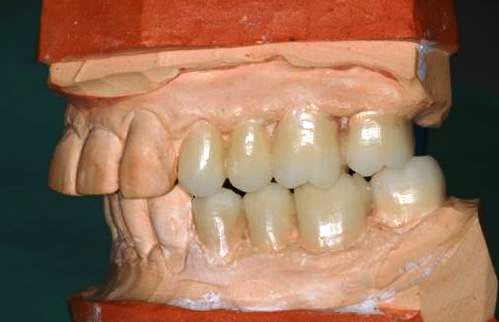

début du Waxup.

Pour les incisives du bas, je pense diminuer le bord libre.

reste à tailler le bloc antérieur.

L'avis des spécialistes en esthétique sera le bienvenu.

Les wax up sont très beaux ! j'aimerais bien que mon prothésiste me fasse des wax up bicolore comme ça...

si on veut chercher la ptite bête :

secteur gauche on a une classe 2 d'Angle molaire : donc dans l'idéal la cuspide de 25 devrait légèrement être mésialée.

Et la cuspide distale de 26 légèrement plus petite pour respecter la courbe de spee.

Mais c'est vraiment pour chercher la petite bête.

Merci pour les waxups, j'ai fait la mise en place et Brigitte la finition.

Pour la couleur, c'est un peu un hasard, mais c'est vrai qu'en photo ça rend bien.

Pour 25/26 c'est exact et la cuspide distale de 47 remonte trop...

pardon pxav , mais tes waxups , ça va pas du tout !

il faut vestibuler le haut considerablement et meme un peu le bas .tout est verouillé pire qu'avant .il faudrait sortir les cuspides vest d'au moins 2 mm minimum .donner un peu d'air en decalage lateral immediat .

je n'ai pas l'impression que les modeles soient en centrée .

je ne comprend l'interet du wax up a cette etape du cas !!!